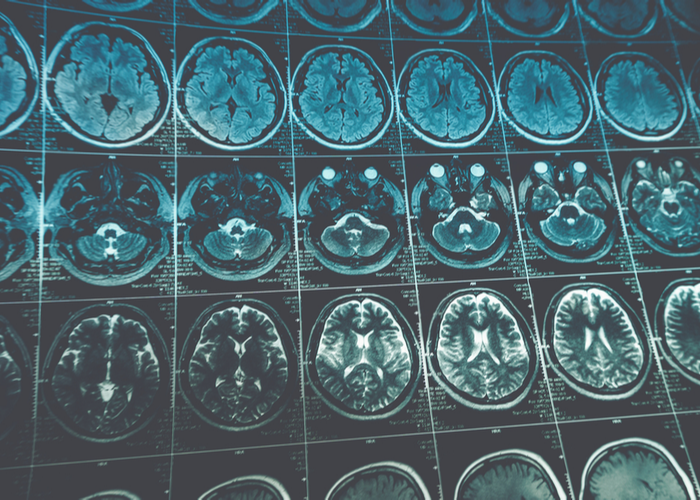

- MRI scan - imaging scan using a computer and a powerful magnet to make cross-sectional pictures of your body